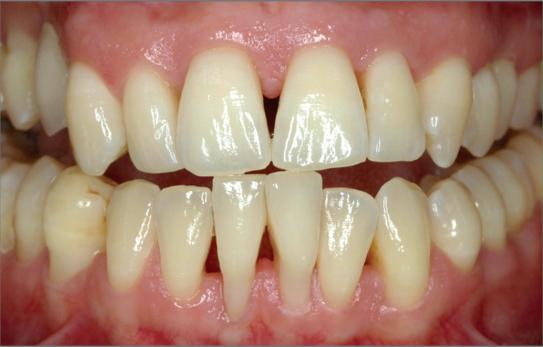

All-on-Six: een duurzame oplossing voor volledige rehabilitatie in de bovenkaak

Een gebit kan volledig falen of ernstig achteruitgaan door een combinatie van cariës, endodontische problemen of parodontale aandoeningen. In dergelijke gevallen is een totaalextractie vaak de enige optie. Aangezien een volledige prothese in Nederland wordt vergoed vanuit de basisverzekering, is dit vaak de eerste keuze. Uit onderzoek van Cawood & Howell (1998) blijkt echter dat alveolair bot resorbeert na extractie. In de eerste drie maanden treedt vooral horizontale resorptie op, gevolgd door verticale resorptie. Dit proces wordt geclassificeerd van klasse II (direct na extractie) tot klasse VI (volledige verticale resorptie). Naarmate het botvolume afneemt, volgt de omliggende mucosa deze resorptie. Hierdoor verliest de mucosa uiteindelijk ondersteuning, wat leidt tot een beweeglijke, zogenaamde flabby ridge. Bij ernstige resorptie kan een prothese onvoldoende houvast bieden tijdens het spreken en eten. Om dit probleem op te lossen, worden implantaten vanuit de bijzondere tandheelkunde vergoed, zodat patiënten een klikprothese kunnen krijgen. Deze protheses worden doorgaans goed gefixeerd met een stegconstructie of drukknoppen.

Het grote voordeel is dat de financiële bijdrage voor patiënten beperkt blijft. Het nadeel is echter dat patiënten lang moeten wachten voordat ze in aanmerking komen voor implantaten en in de tussentijd een losse prothese moeten gebruiken. Een alternatief is een vaste brug op implantaten. Een voordeel hiervan is dat er direct gestart kan worden zodra de patiënt akkoord geeft. Het grootste nadeel is echter de hoge kosten, die grotendeels voor eigen rekening komen. In dit artikel worden de indicatie, de spreiding van implantaten en de vervaardiging van de suprastructuur besproken.

Casus

Een 54-jarige, gezonde man (niet-roker) had in het verleden volledige kroon- en brugwerken in de boven- en onderkaak. Een halfjaar eerder kwam de brug in de bovenkaak los door cariës onder de pijlers. De onderkaak vertoonde eveneens aanhechtingsverlies en pockets dieper dan 6 mm bij enkele elementen. De patiënt gaf direct de voorkeur aan een vaste

brug op implantaten boven een prothese. Vanwege gegeneraliseerde parodontitis in de onderkaak werd het volgende behandelplan opgesteld: